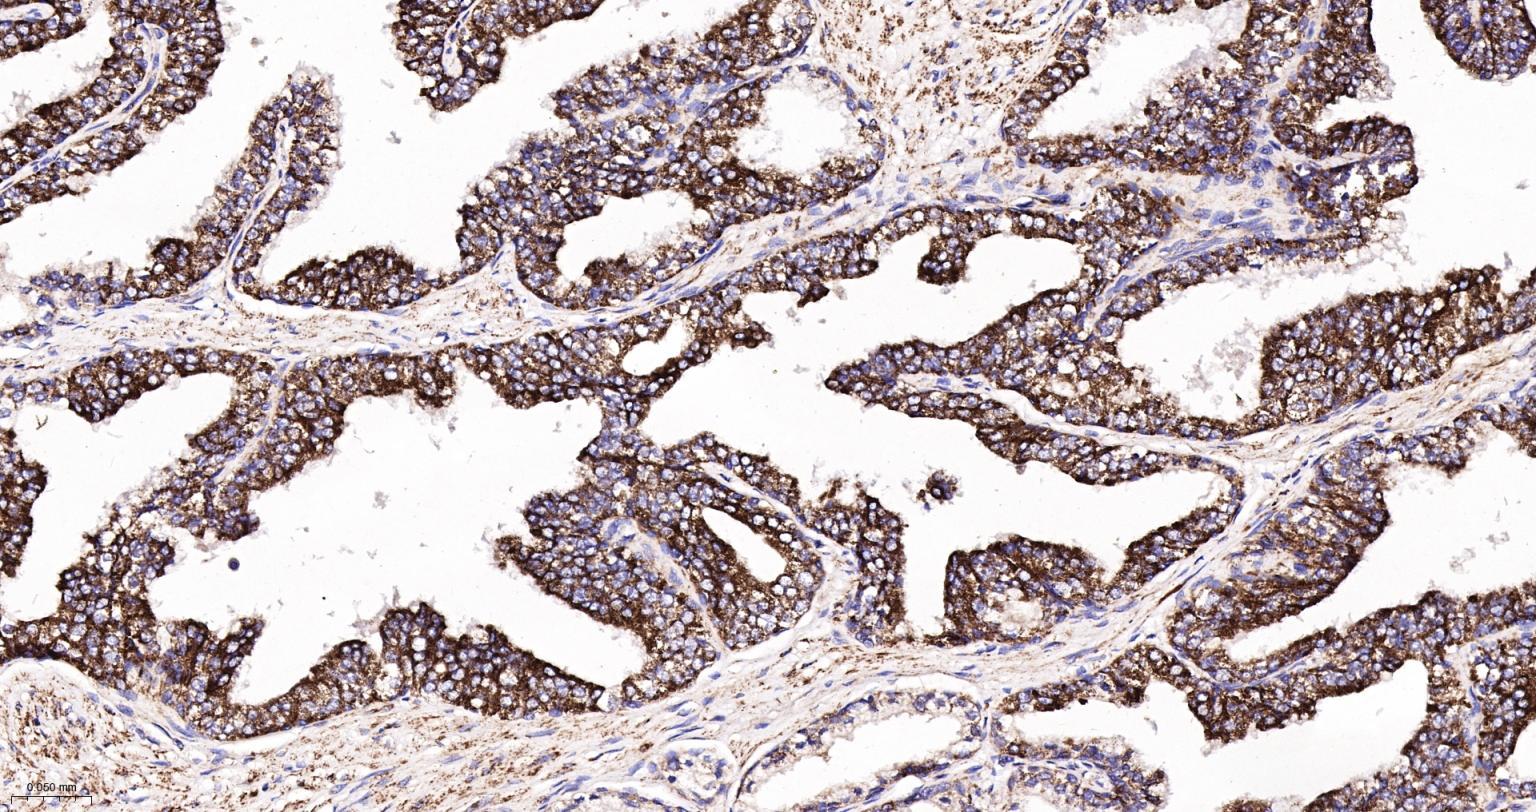

Paraformaldehyde-fixed, paraffin embedded Human Prostate Cancer; Antigen retrieval by boiling in sodium citrate buffer (pH6.0) for 15 min; The section was incubated with IDH2 Monoclonal Antibody, Unconjugated (bsm-61585R) at 1:200 overnight at 4°C, followed by conjugation to the bs-0295G-HRP and DAB (C-0010) staining.